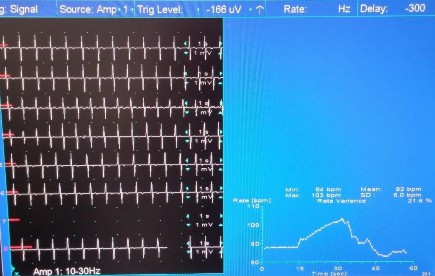

Hình 2.7 Biến thiên nhịp tim bất thường với test Valsalva (Chỉ số Valsalva = 1,1)

(Nguồn: bệnh nhân Trần Hữu L, năm sinh 1967, thực hiện test tại phòng điện cơ, bệnh viện Chuyên Khoa Ngoại Thần Kinh Quốc Tế)

Tỷ số Valsalva = nhịp tim nhanh nhất của pha 2/ nhịp tim chậm nhất của pha 4 (khoảng cách R-R dài nhất của pha 4/ khoảng R-R ngắn nhất của pha 2)

Cho bệnh nhân hít sâu vào và thổi mạnh vào một cái ống có lực cản (nối với máy đo huyết áp), sao cho tạo được và duy trì áp lực 40mmHg trong 15 giây. Sau đó, cho bệnh nhân nghỉ 3 phút là lặp lại nghiệm pháp này thêm 2 lần nữa. Chọn tỷ số Valsalva cao nhất trong 3 lần làm kết quả cuối cùng.